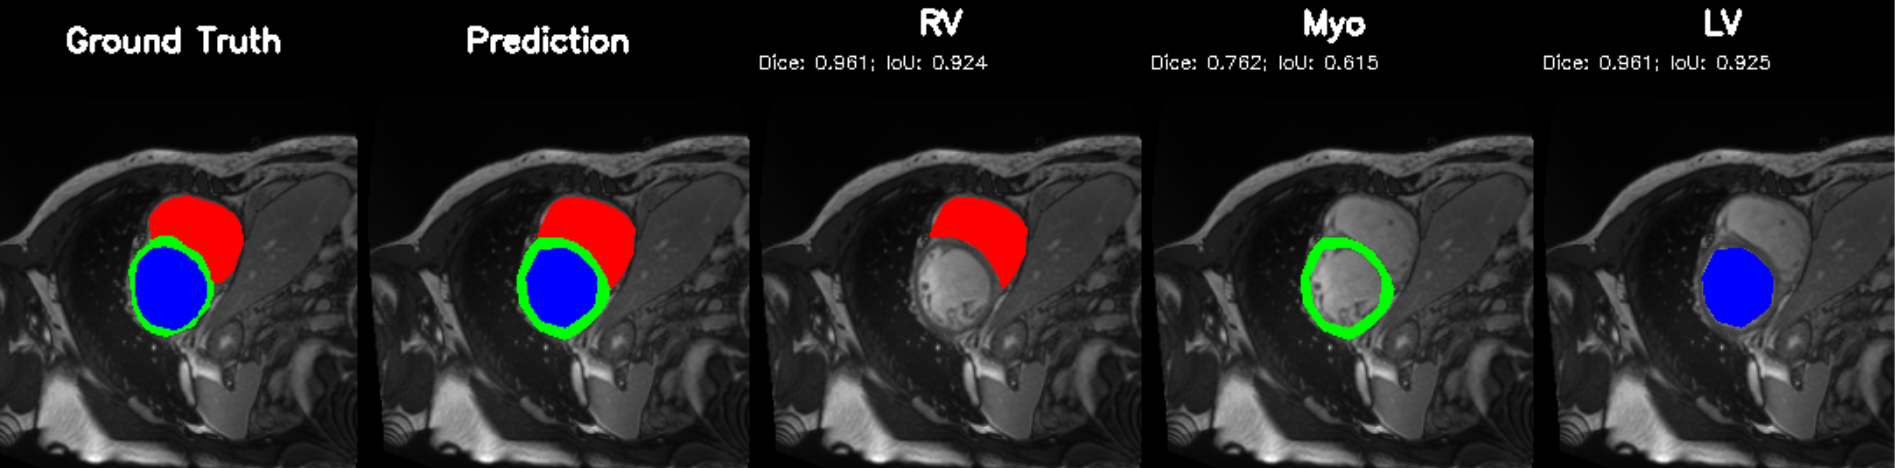

5.2 M&Ms Cine-MRI Generalization

Figure 8 illustrates segmentation outputs on the M&Ms (Multi-Centre, Multi-Vendor) cine-MRI dataset, which exhibits both contrast variation and vendor–specific acquisition differences compared to ACDC. The model retains consistent ventricular geometry, recovering LV and Myocardium structure without retraining, mirroring the zero-shot Dice performance of 74.8% (Table 11). Boundary thickness remains physiologically accurate, with only minor degradation in the right ventricle, an expected behaviour under cross-domain shifts and also reflected quantitatively in the ablation-driven robustness improvements from normalization and loss design. These results demonstrate that PULSE does not overfit to a single scanner distribution but instead transfers cardiac structure priors across unseen clinical environments.